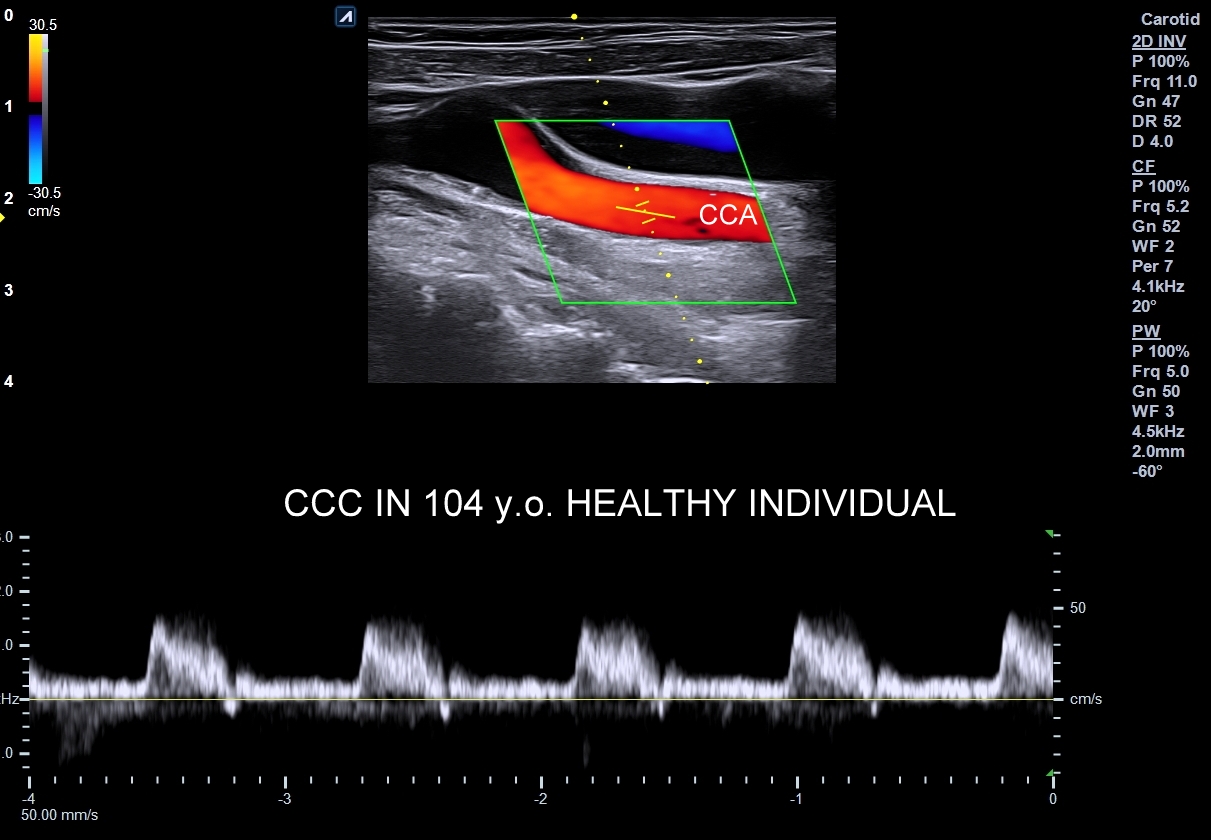

Oprócz przepływów typowo niskooporowych oraz typowo wysokooporowych istnieją profile przepływów o pośredniej charakterystyce, np. w tętnicy szyjnej wspólnej. Z kolei w przypadku tętnic kręgowych w zależności od ich szerokości fizjologicznym jest obserwowanie zarówno profilu niskooporowego w przypadku dużej średnicy, jak i wysokooporowego w przypadku małej średnicy.

- Profile o umiarkowanej pulsacyjności różnią się od wcześniej omówionych tym, iż przepływ w fazie rozkurczowej utrzymuje się, jednakże ma niższe prędkości i może być przerwany drobnym, wczesnodiastolicznym odwróceniem przepływu. Profile tego typu występują w tętnicach unaczyniających np. twarz, jelita, trzustkę.